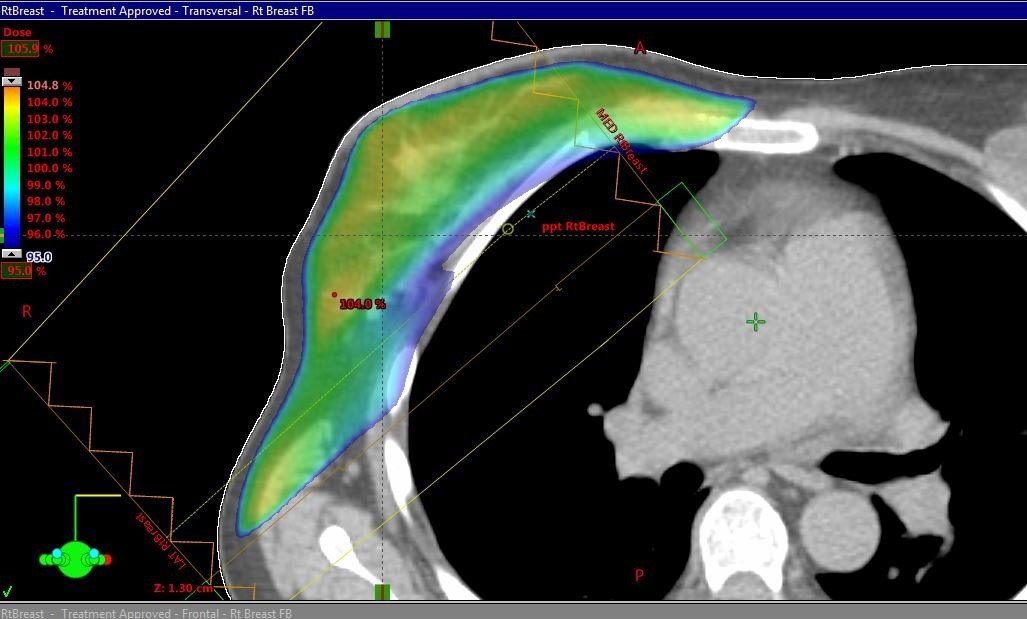

One of the few radiation dosimetry techniques that has not thoroughly changed over time. Whole breast radiation has been considered the standard of care using three-dimensional radiation planning techniques. Novel approaches with deep inspiration breath hold with gating reduce radiation to healthy lung and heart.